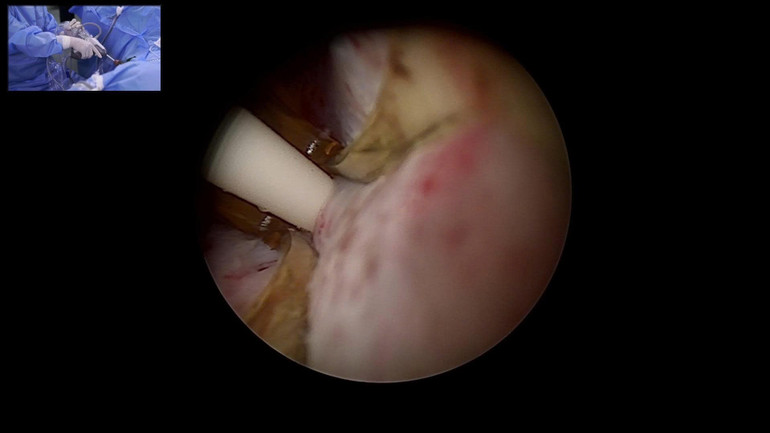

Trong khuôn khổ Hội nghị thường niên Hội Tiết niệu-Thận học Việt Nam khu vực phía Bắc (VUNA-North), dưới sự chỉ đạo của Tiến sĩ, bác sĩ Nguyễn Minh Tuấn - Trưởng khoa Phẫu thuật Tiết niệu, Bệnh viện Bạch Mai đã triển khai thành công 2 ca mổ thị phạm sử dụng liệu pháp nhiệt hơi nước (Rezūm) - phương pháp điều trị BPH ít xâm lấn nhất và mới nhất hiện nay trên toàn cầu.

Hai ca mổ thị phạm được truyền hình trực tiếp với sự tham dự của nhiều giáo sư, chuyên gia đầu ngành trong và ngoài nước, cùng các bác sĩ chuyên khoa tiết niệu từ các bệnh viện tuyến trung ương và tuyến tỉnh đến tham dự, quan sát và học tập kỹ thuật mới.

Theo đó, kỹ thuật sử dụng năng lượng nhiệt từ hơi nước ở khoảng 103 độ C. Hơi nước được đưa chính xác vào mô tuyến tiền liệt phì đại, phá hủy có chọn lọc phần mô bệnh mà không cần cắt bỏ. Mô hoại tử sẽ được cơ thể hấp thu tự nhiên theo thời gian, giúp giải phóng tắc nghẽn và cải thiện dòng tiểu.